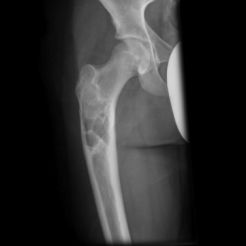

Kemikte aşırı zayıflık oluşunca patolojik kırık gelişebilir. Uyluk kemiği üst ucunda lezyonun geliştiği fark edilmez ise çoban asası görüntüsü meydana gelir. Düz grafide buzlu cam görüntüsü tipiktir. Genellikle hastaların şikayeti yoktur. Şişlik ve ağrı şikayeti gelişebilir. Fibröz displazi iskelet sisteminin gelişimi ile birlikte büyür. İskelet büyümesi tamamlanınca lezyonun gelişimi yavaşlar.